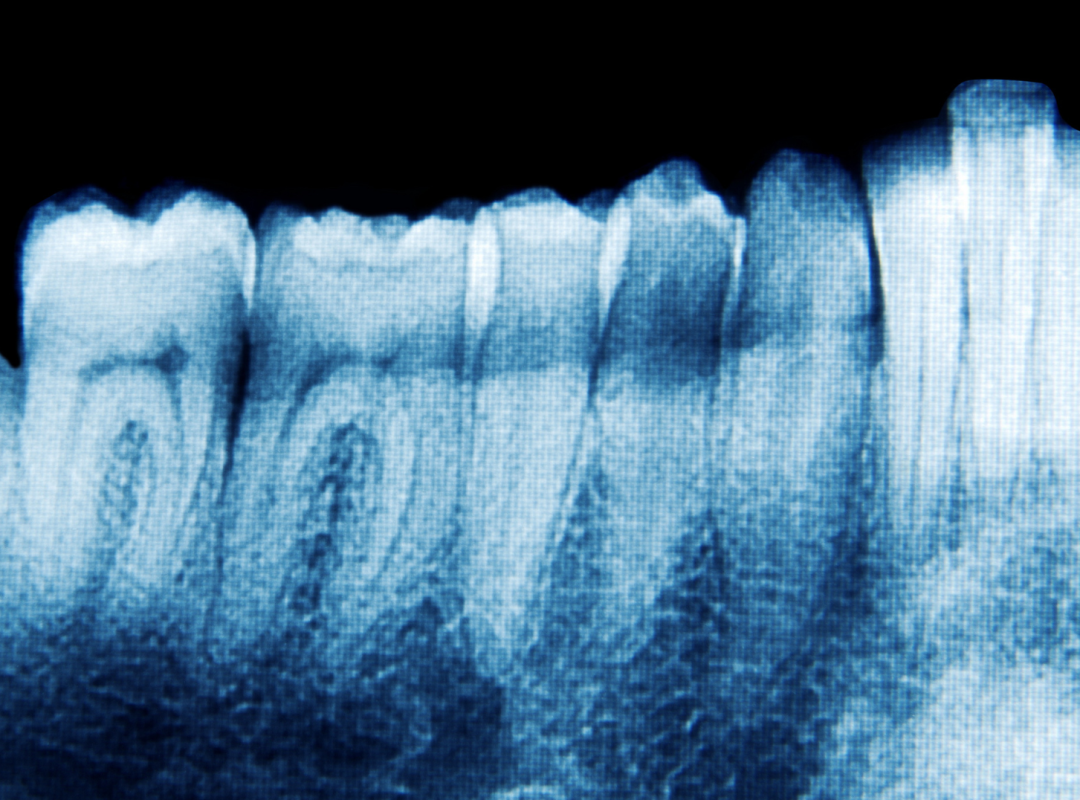

Le traitement de canal moderne est précis et indolore, réalisé sous anesthésie locale. Après isolation stérile de la dent, le praticien, guidé au microscope, retire la pulpe infectée. Les canaux sont nettoyés, mis en forme et désinfectés avec des instruments micro‑dentaires. Une fois asséchés, ils sont scellés par un matériau biocompatible et obturés provisoirement avant la restauration définitive ultérieure.

- Imagerie 3D (CBCT) : Cette technologie permet une analyse détaillée de l’anatomie des racines, utile pour les cas complexes ou les actes chirurgicaux.

Le microscope offre un grossissement jusqu’à 25× et un éclairage intense. Il permet de repérer des canaux accessoires, des fractures invisibles à l’œil nu et d’assurer une désinfection plus précise, donc un meilleur pronostic.